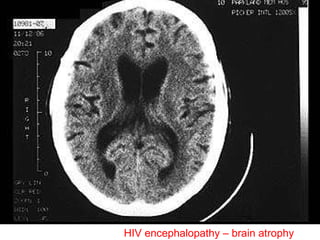

HIV neurologic disease Acute  aseptic meningitis subacute and chronic:  HIV  meningoencephalitis – AIDS-dementia complex, vacuolar myelopathy, myopathy and peripheral neuropathy

HIV encephalopathy – brain atrophy